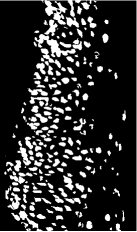

According to the SLIC method applied in this study, the cellular structures become more compact and can be separated from the background when each obtained SEP image is expressed with 3000 superpixels. A cellular structure in cervical precursor lesion is approximately . A crucial point to note here is that the superpixels’ sizes should not exceed the size of cellular structure. As can be calculated from the Eq.1, choosing at least 2000 superpixels will guarantee most of the superpixels to not exceed the size of a cellular structure. Less number of superpixels cause overlapping cells. It can be quite difficult to distinguish cellular structures, especially those close to the BM. Since the superpixels which represent the cellular structures are darker than the superpixels which represent the background, the elimination of the unwanted pixel groups (fat-like tissue) above a certain threshold level clears the background. At this stage, small artifacts similar to the cellular structures and some inflammation can remain with the cells as a foreground information. These structures can be eliminated with a morphological size operation that can be applied to the binary image after segmentation stage. Final segmentation result of a sample SEP image patch obtained from the data set is shown in Fig. 8.

Overlapped cells are intensively present on the SEP image patches. The problem of overlapping of cells should be handled in order to obtain the morphological characteristics of the cell nuclei. Binary images segmented by using SLIC algorithm usually consist of small cellular-like noisy parts. These unwanted small pixel groups are eliminated by an automatic method, which clears pixel groups smaller than 50 pixel. Therefore, the circumference of the cells is also quite rough after the segmentation process. As shown in Fig. 9(a), the closing process has been applied to make the binary image more compact. In order to obtain cell centers, the distance transform is applied to get local maxima shown in Fig 9(c). Local maxima are estimated by using Algorithm-1.